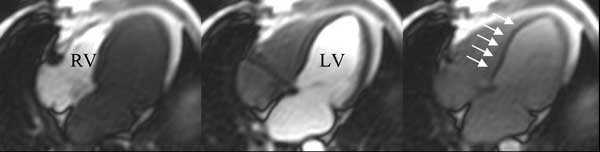

Die Wissenschaftler haben außerdem eine weitere wichtige Voraussetzung geschaffen, um diese Methode für die klinische Anwendung fit zu machen. Bislang konnten nur maximal drei Schichtbilder von der Herzdurchblutung beim Menschen aufgenommen werden. Mit der in Würzburg entwickelten Auto-SENSE-Technik, einem so genannten parallelen MR-Bildgebungsverfahren, gelingt es nun aber innerhalb weniger Sekunden, die Durchblutung des ganzen Herzens lückenlos aufzuzeichnen.

"Mit Hilfe dieser neuen MR-Technik wird es möglich sein, auch kleine Durchblutungsstörungen oder eine Minderdurchblutung nur der inneren Schichten des Herzmuskels quantitativ nachzuweisen", so der Radiologe PD Dr. Jörn Sandstede vom Würzburger Universitätsklinikum. Nach seiner Einschätzung wird die Bestimmung der Herzdurchblutung mittels Magnetresonanz-Tomographie in wenigen Jahren aus der Diagnostik von Herz-Kreislauf-Erkrankungen nicht mehr wegzudenken sein. Als nächstes strebt die Arbeitsgruppe am Institut für Röntgendiagnostik die Umsetzung ihrer Forschungsergebnisse in die Patientenversorgung an.